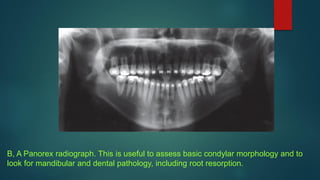

B, A Panorex radiograph. This is useful to assess basic condylar morphology and to

look for mandibular and dental pathology, including root resorption.